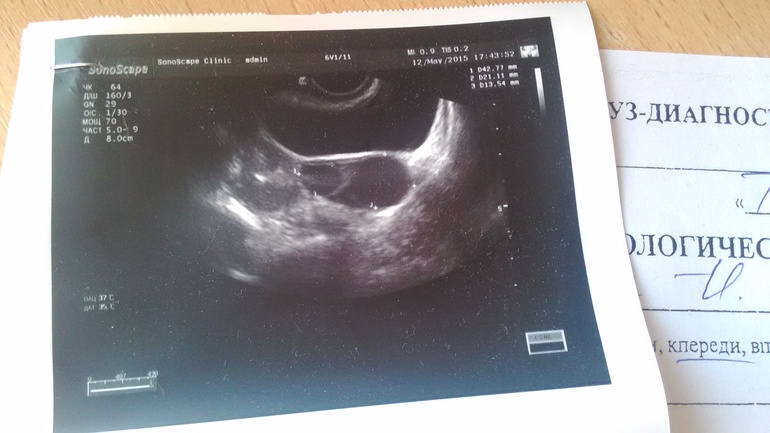

Только по тестостерону не судят о возможности беременности, так как даже при повышенном тестостероне может сохраняться овуляция. Но в вашем анализе еще обращает на себя внимание соотношение ЛГ и ФСГ, а вместе с тестостероном такие показатели могут отражаться МФЯ. У вас есть результаты последнего УЗИ?

Узи было во время задержки

Это делала у другого врача

Щелково

Ну это то, о чем я говорила — признаки МФЯ, подтвержденные еще и УЗИ. Отсюда и задержки. Ваши анализы полностью соответствуют УЗИ. Скорее всего, цикл ановуляторный, это также является признаком МФЯ. Какое ВЫ сейчас получаете лечение? Если Вам интересно продолжить общение, пишите, пожалуйста, в группу. мне так проще отвечать на вопросы. Спасибо! http://www.babyblog.ru/community/post/viferon/237599